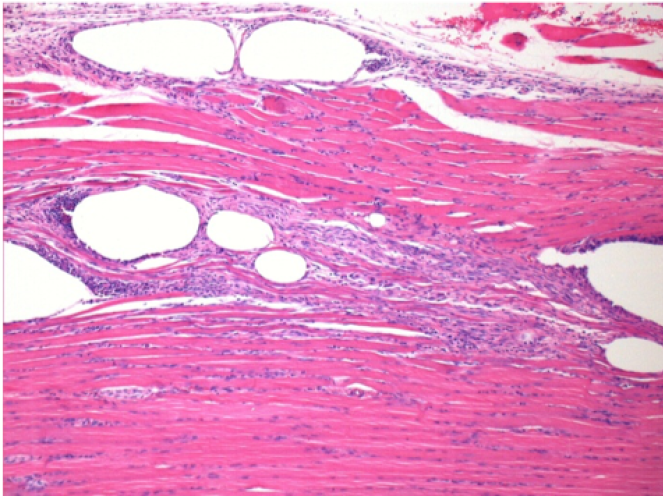

10 days after Endopeel Injection 0.1ml in the right pretibial muscle.

Here you may see the formation of the vacuoles which are surrounded by lymphocytes. Vacuoles are different from tissue necrosis . The presence of lymphocytes is related to the permeability of the cell membranes.